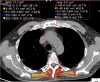

Fig. 16

Axial CT image shows bilateral pleural plaques in a 76-year-old male with previous asbestos exposure (A). Three-dimensional reconstructions show the typical distribution of the pleural plaques (B, C)